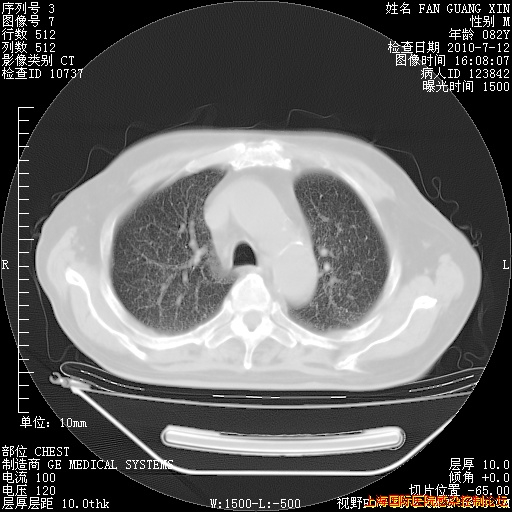

今天复查CT

今天CT

整整相隔30天的肺部CT好像有所好转啊。甲强龙减量第3天,需要观察体温。